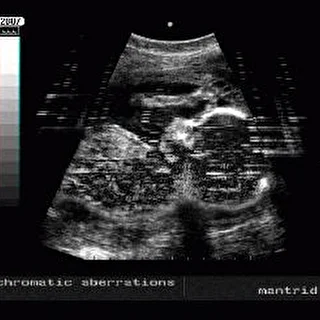

- Эти minimal drone треки были созданы в ходе экспериментальной работы с графическими фонограммами. В работе не использовались традиционные секвенсоры, семплеры и синтезаторы. Преобразование графических данных в аккустические выполнялось методом програмного синтеза натуральных обертонов. Звук прошел минимальный процессинг (Waves TrueVerb). В эксперименте по преобразованию графики в звук использовались УЗ-сонограммы органов человека, плода, раковых опухолей различной локализации полученные при помощи аппарата ультразвуковой диагностики; форетические пластины ДНК-типирования и генетические карты вируса папиломы человека (ВПЧ), вируса гепатита С (HCV) и ВИЧ.

- Chromatic aberreations (CDR)